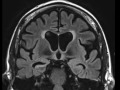

Mesial Temporal Sclerosis

In this patient with chronic seizure disorder, we see volume less of the right hippocampus with distortion of the normal morphology, increased T2/FLAIR hyperintensity, and corresponding dilatation of the temporal horn of the right lateral ventricle, consistent with mesial temporal sclerosis.